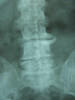

Artrosis cervical.